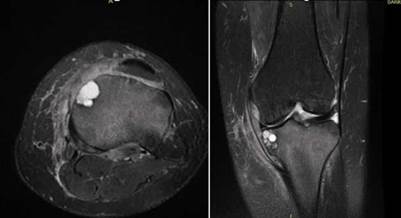

On the other hand, magnetic resonance imaging (MRI) (Figure 2) showed a prominent and confluent bone and subchondral cysts of 18mm in diameter in the medial tibial plateau, as well as a diffuse increase in bone marrow signal intensity and changes associated with disuse osteopenia.

Figure 2 MRI of the left knee in T2 mapping sequence in axial and coronal view showing a cystic lesion in the medial tibial plateau and a diffuse increase in the signal intensity of the tibia.